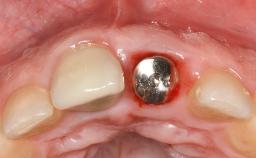

This case describes both a surgical and an anti-infective approach for the management of peri-implantitis, including treatment of the entire dentition to eliminate any deep periodontal pockets that could serve as reservoirs for bacterial re-colonization at the implant site. A 65-year-old female patient was referred to the periodontist in 2013 for assessment and management of an infection at implant 12. On examination, probing depths at implant 12 were 11 mm with suppuration and bleeding on probing.